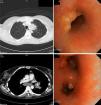

A 45-year-old woman who had been resident in India until 8 months previously, presented with clinical symptoms for the last 3 months of daily fever (up to 38°C), anorexia, weight loss, dry cough, and dyspnea that did not improve after 7 days of treatment with amoxicillin–clavulanic acid. She had good general health upon examination, the only remarkable finding being two mobile, rubbery subcutaneous nodules sized 1cm in the left upper quadrant that were slightly painful but with no signs of inflammation, and a similar one in the left hand. Blood tests revealed anemia, leukocytosis and thrombocytosis. Chest radiography showed a mass in the anterior mediastinum described in the computed tomography (CT) report as “mass in the left upper lobe and ipsilateral hilar region, with anterior mediastinal infiltration causing stenosis of the bronchial lumen; ipsilateral subcarinal and paratracheal lymphadenopathies, accompanied by multiple independent nodules in the left lung, pleural implants, and subcutaneous abdominal nodules”. Bronchoscopy revealed inflamed mucosa with implants of tumor-like appearance and left bronchial stenosis. Malignancy was ruled out after biopsy, but both bronchial biopsies and one of the abdominal nodes showed non-necrotizing granulomas. Cultures were initially negative, but then multi-susceptible Mycobacterium tuberculosis grew in sputum. Accordingly, the patient was diagnosed with disseminated TB with tumor-type endobronchial and skin involvement. The patient improved rapidly with TB therapy and corticosteroids. Bronchoscopy was normal at 6 months, while the CT showed only residual thickening of soft tissues (Fig. 1).

Endobronchial TB occurs in 5%–40% of active pulmonary TB, although it is underdiagnosed.2,3 The cause is implantation directly from an adjacent cavity, a focus of tuberculosis or a mediastinal lymph node, or by bloodborne or lymphatic spread.3,4 Symptoms include cough (71%–100%), fever (50%), weight loss (30%), hemoptysis (18%–25%), dyspnea, chest pain and anorexia.2,4,5 Both the duration of symptoms and the disease progression are variable and can range from complete resolution to the appearance of bronchiectasis, bronchial obstruction or atelectasis. The most useful microbiological test is bronchoalveolar lavage, which outperforms sputum.2–5 X-ray may show alveolar infiltrates (35%–43%), nodules (25%), cavitated lesions (12%), pleural effusion (9%) or hilar thickening (7%), but it may be normal in 10%–20% of cases.2,3 CT is useful for assessment of disease extension, degree of bronchial obstruction and progress, and may replace bronchoscopy during follow-up,4 although it is the imaging study of choice during diagnosis.

Chung and Lee classify TB into seven subtypes3: caseating (12%–43%), edematous-hyperemic (14%–44%), fibrostenotic (6%–10.5%), tumoral (10.5%–30%),3–5 granular, ulcerative, and nonspecific bronchitis type. The first four have a poorer prognosis, because of associated bronchial stenosis.3 These types seem to represent different stages of the same disease, starting with granulomas and submucosal inflammatory lesions that progress to masses, fibrosis and airway stenosis.4,5 The tumoral subtype has endobronchial masses, with a hemorrhagic surface and a necrotic outer layer, simulating squamous carcinoma. Risk factors for residual bronchial stenosis are age over 45 years, fibrostenotic type, and late diagnosis.2,5 Treatment includes endoscopic dilation, mechanical resection, or stenting combined with corticosteroids. The latter seems to be effective in the early stages and the caseating/tumoral forms,4 so for this reason they were used in our patient, who achieved total recovery.